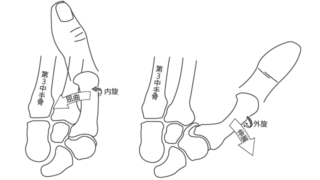

CMC 関節形成術は、 CMC 関節関節炎の治療に使用されます。物を掴む、つまむ動作など、現在痛みを引き起こしている動作を行うのに役立つ場合があります。

- 靱帯再建:損傷した靱帯の一部を、別の結合組織片から作成した移植片で置き換えます。